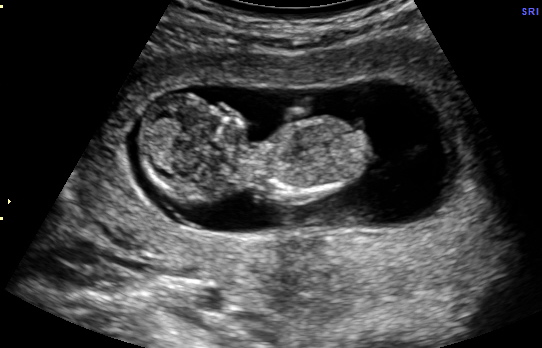

I am currently 15 weeks and have an ultrasound in 4 weeks to find out gender. The pictures below are at 12 weeks. I have 3 awesome boys and would love a girl for my final babe. Thoughts? Thanks so much!Attachment 11991Attachment 11990